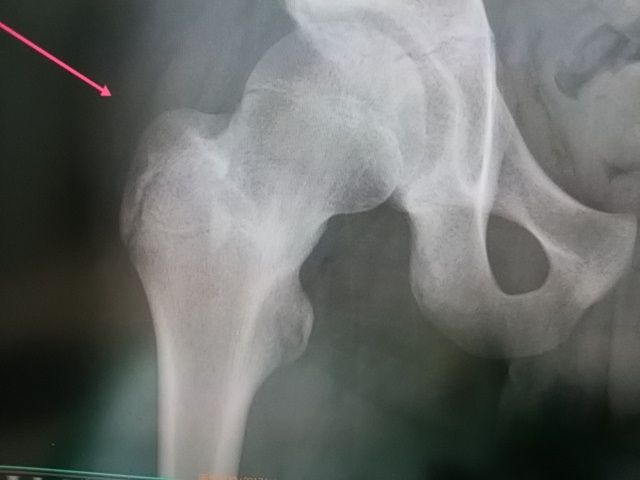

大腿部の疲労骨折はあまりおこりにくい

ですが、難治性のため、整骨院から

紹介いただきました。

骨癒合も良好で競技復帰していきます。